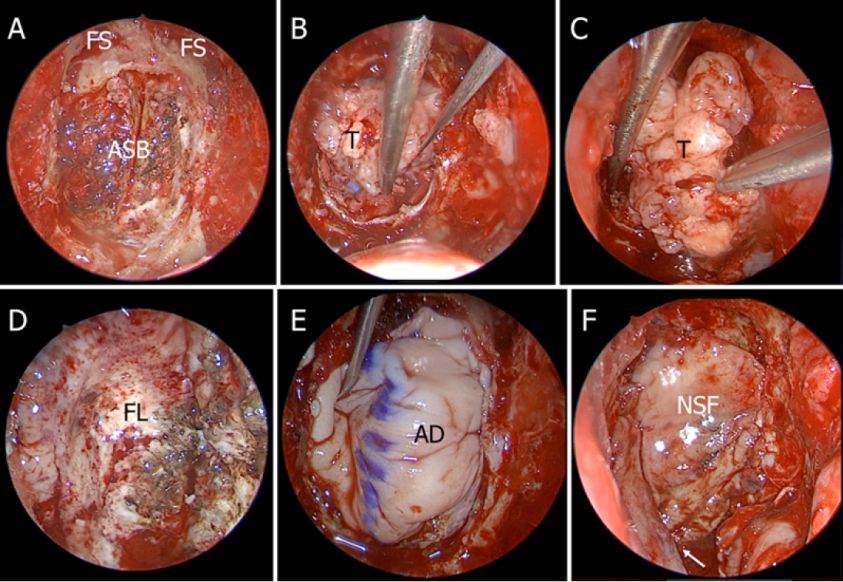

图1. A-C.术前MRI显示OGM;D-F.经额底入路切除OGM术后的MRI成像。